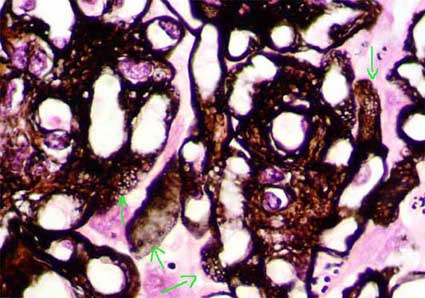

Figure 1. In GNM the alterations are demonstrated, mainly, in the capillary walls; here they appear thickened and with rigid aspect (green arrows). In some cases we find variable degrees of mesangial hypercellularity (blue arrows), in these cases we must consider the possibility of a secondary MGN. (H&E, X.400).

Figure 2. The characteristic finding that allows the diagnosis in most of cases are the perpendicular projections in the outer aspect of the GBM, seen with silver stain (arrows). In initial stages when spikes are not still formed may not be possible to do the diagnosis without immunofluorescence or electron microscopy. (Methenamine-silver, X1000).

Figure 3. In cases of large subepithelial deposits is possible, in thin sections and with a good trichrome stain, to see the immune deposits with a characteristic red color (fuchsinophilic) (arrows). Even in initial stages, without “spikes”, this finding allows us to make the diagnosis of MGN. Unfortunately it is not frequent to see these deposits with light microscopy (Masson’s trichrome, X1000)..

Figure 4. In sections in which the GBM appears tangential it is possible to see spaces or holes (arrows); these holes are due to the presence of immune deposits, negative with the silver, surrounded by BGM-like (positive with the silver). Many of these holes correspond to deposits completely surrounded by the “spikes”. (Methenamine-silver, X1000).